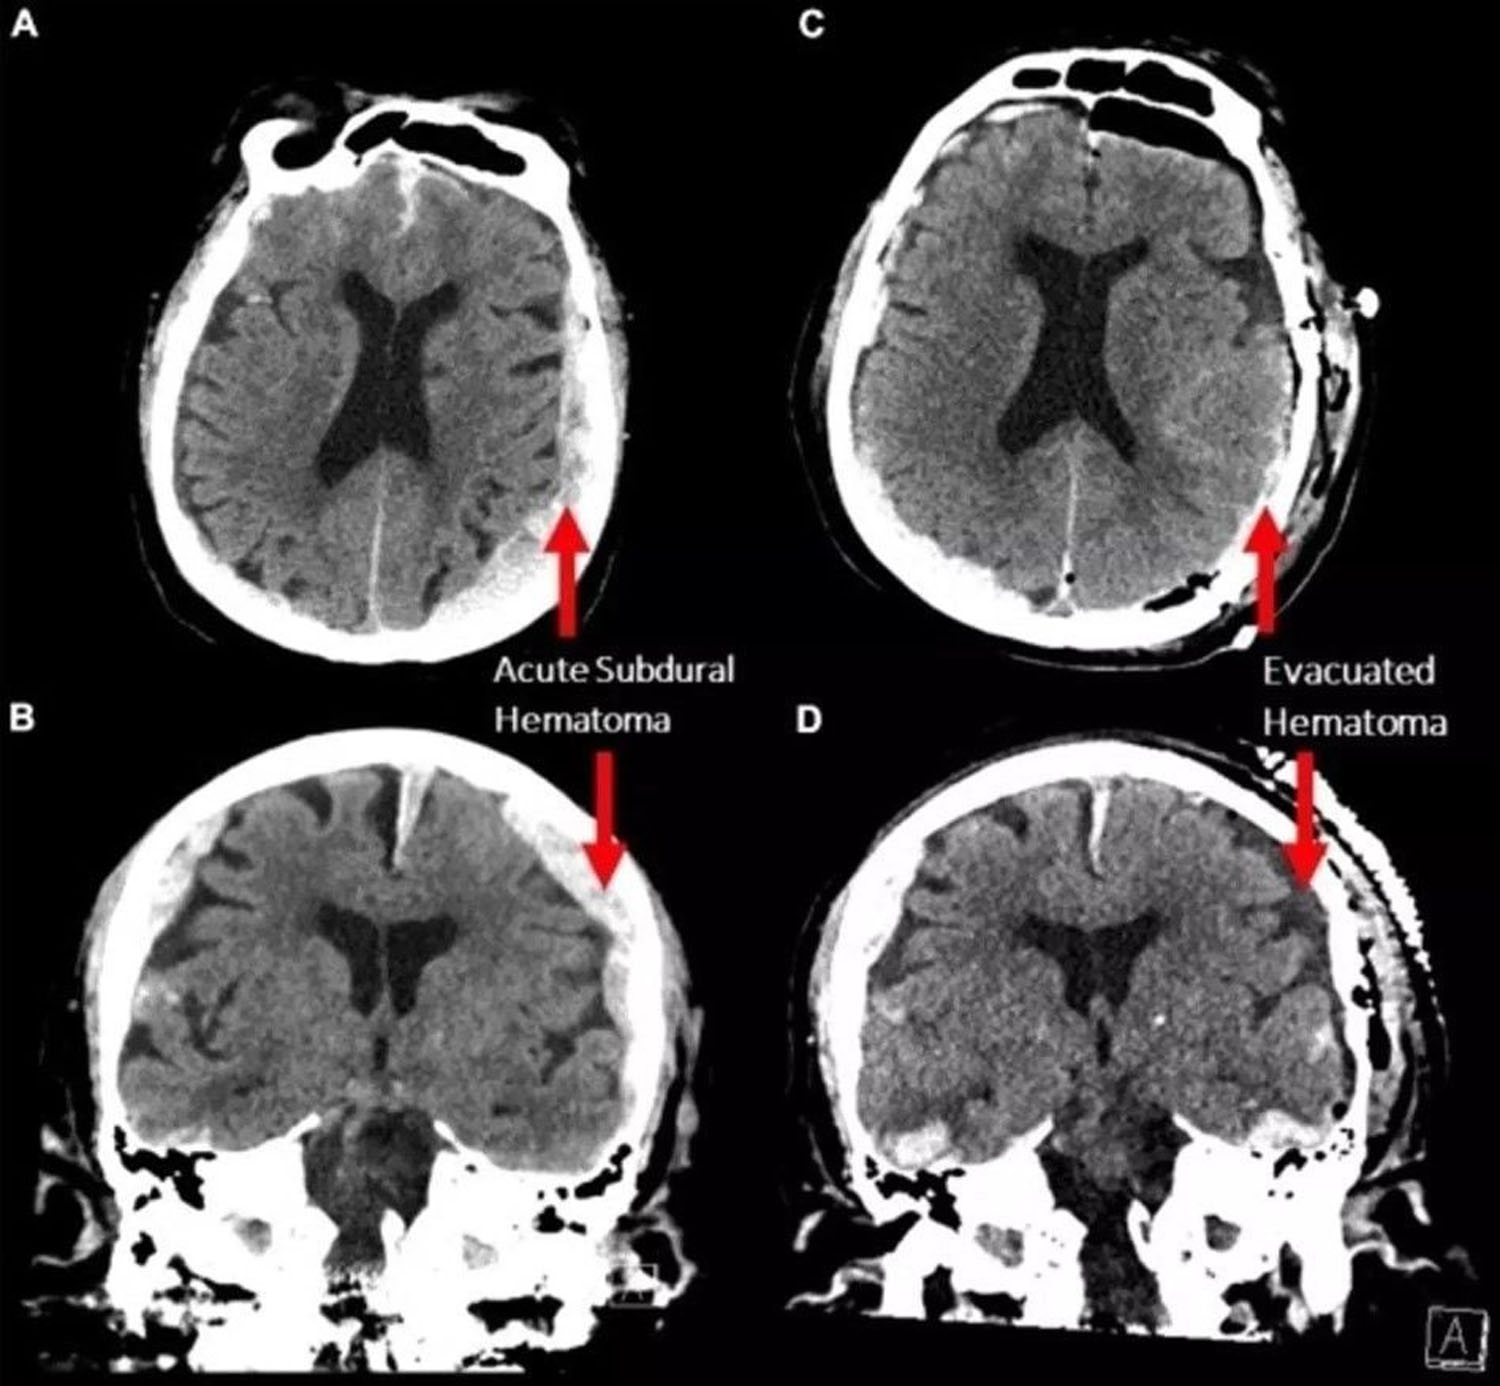

(1)Vankuverio (Kanada) mokslininkai stebėjo 87 metų paciento, kuris sirgo epilepsija, bet jiems stebint netikėtai mirė dėl širdies smūgio, smegenis.

Remdamiesi elektroencefalogramos (EEG) rezultatais, jie galėjo nustatyti, kas vyko jo smegenyse paskutinėmis jo gyvenimo minutėmis - konkrečiai, 30 sekundžių prieš ir po to, kai nustojo plakti širdis.

Tyrimas parodė, kad panašūs žiurkių smegenų bangų pokyčiai mirties metu - tačiau tai pirmas kartas, kai tai nustatyta žmonėms.